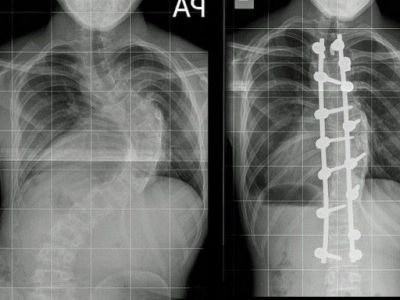

Έφηβος ψηλώνει κάθε βράδυ περίπου δύο πόντους μετά από εγχείρηση σκολίωσης!